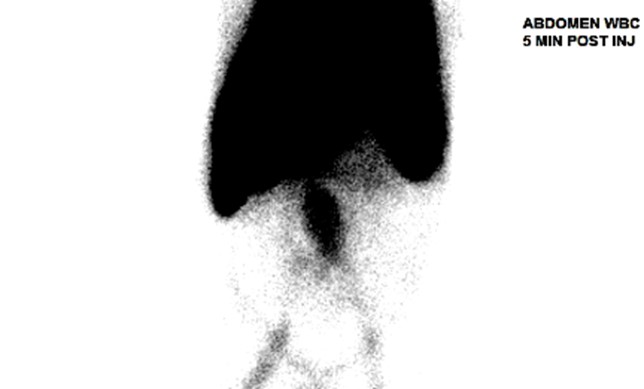

The patient subsequently began to develop abdominal discomfort and new fever spikes. Repeat lab findings showed an increased leukocyte count, and CT angiogram demonstrated a significantly increased size to 7.6 x 9.1 x 13.3cm, concerning for impending rupture and underlying aortitis. Nuclear white blood cell scan was performed and revealed abnormal increased uptake involving the mid and distal abdominal aorta, suggestive of infection. Vascular consultation was obtained, and he successfully underwent percutaneous endovascular aortic repair. He tolerated the surgery well and observed improvement in symptoms, following which he was discharged.

Image 4: Tagged White Blood Cell Scan of Abdomen shows increased uptake in Abdominal Aorta.